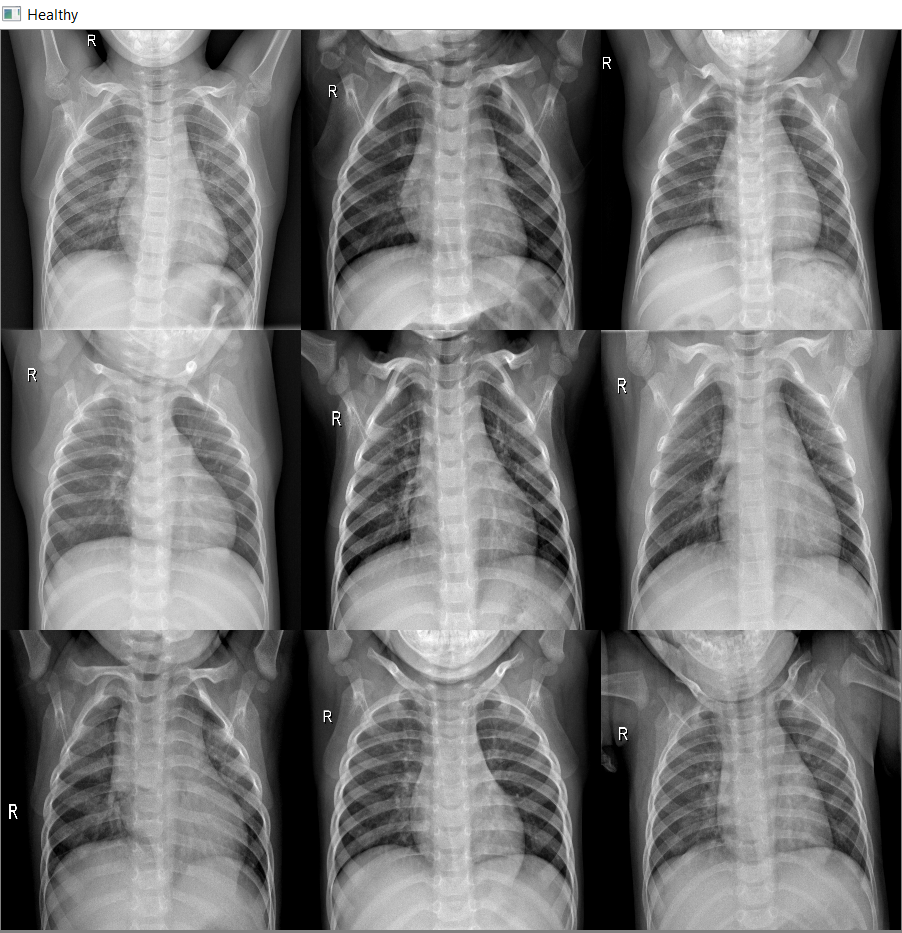

Radiographic and CT Features of Viral Pneumonia RadioGraphics